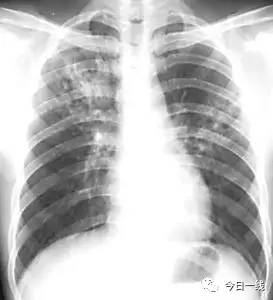

(肺结核 网络图)

深圳市慢性病防治中心结核病防治科科长谭卫国:“结核它是一种通过咳嗽或者飞沫传播的一种慢性传染病,有一部分的病人是没有症状的,可能是通过体检拍胸片才能发现的。”